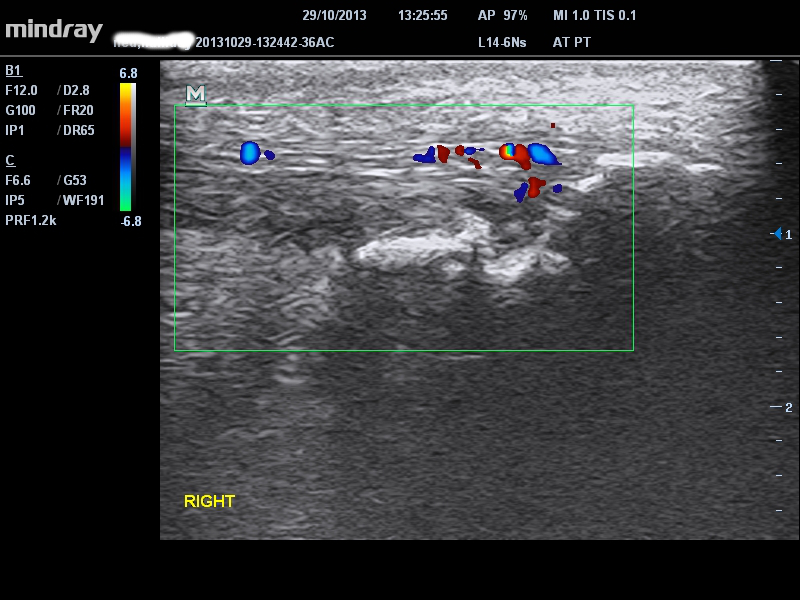

ALMOHADILLA O BOLSA DE GRASA

La almohadilla de grasa puede producir síntomas en forma aislada, comúnmente por compresión en la dorsiflexión, a menudo cuando hay un tendón con un aumento de volumen asintomático pero asociado, tendón accesorio/sóleo bajo o tendón plantar anormal. Por lo general, la bolsa adiposa alrededor de la porción proximal/media del tendón de Aquiles está afectada, en lugar de estarlo más distalmente. El dolor puede ser difuso, medial y lateral o medial solamente. El diagnóstico siempre es clínico y se basa en la palpación diferencial de la almohadilla de grasa y del tendón: ¡simple pero frecuentemente olvidado! Además, la almohadilla de grasa puede que se caliente menos y estar más irritable. La ecografía a veces da señal Doppler principalmente en la almohadilla de grasa, como se ve a continuación, pero este signo no aparece de forma consistente.

single-image

Figura 9 – Señal Doppler en la almohadilla de grasa, pero con un tejido graso predominantemente más profundo en pacientes con síntomas de almohadilla de grasa.